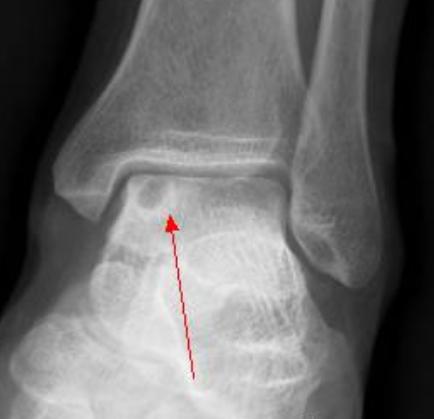

X线:邻近关节面、骨端一侧;囊状骨质破坏,边界清;无骨膜反应及软组织快,有硬化边;骨性关节面完整,关节间隙正常,无退变